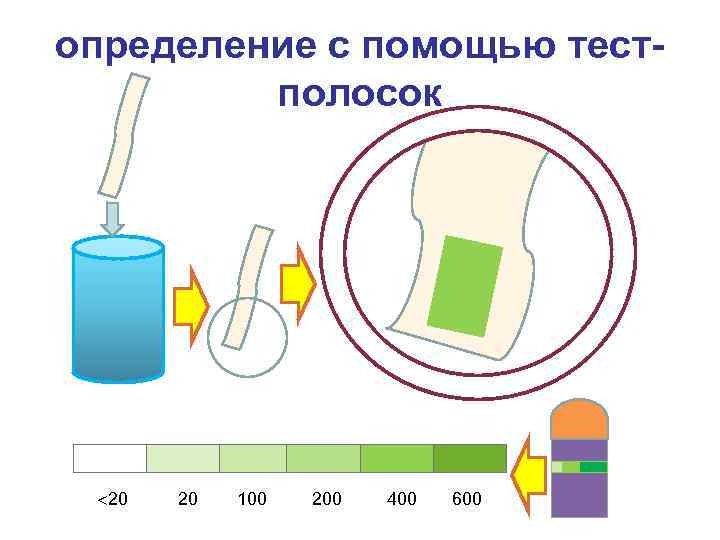

определение с помощью тестполосок 20 20 100 200 400 600

определение с помощью тестполосок 20 20 100 200 400 600